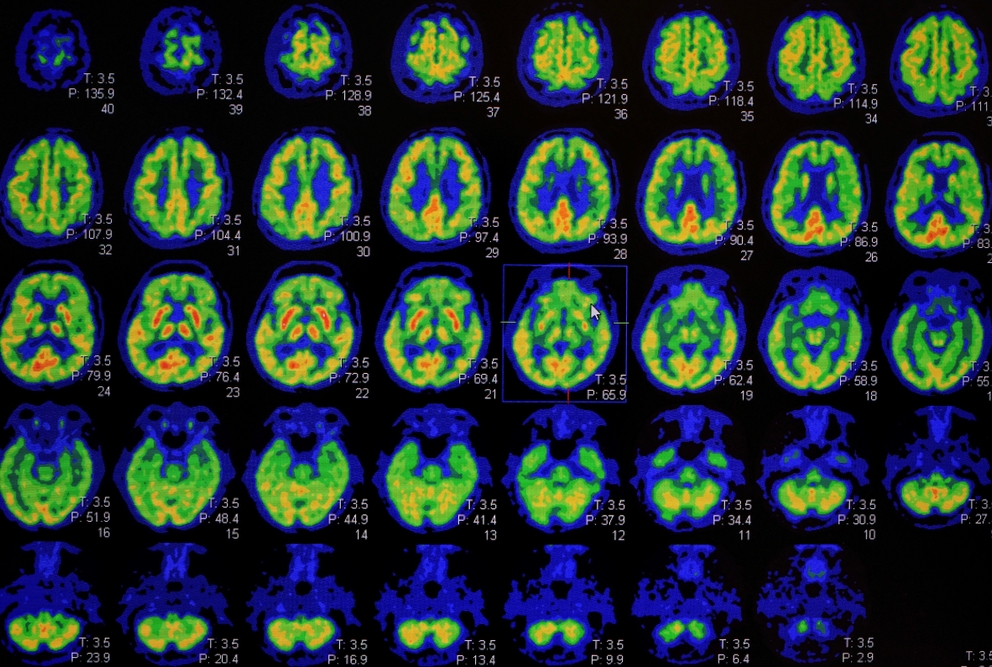

“It isn’t really feasible to run a clinical trial of estrogen therapy for that length of time to look for a dementia-preventing effect,” Dr. Mosconi said. “We need more clinical trials evaluating the effects of midlife hormone therapy on biological indicators of Alzheimer’s disease, which we can now measure using brain imaging and fluids such as blood.”